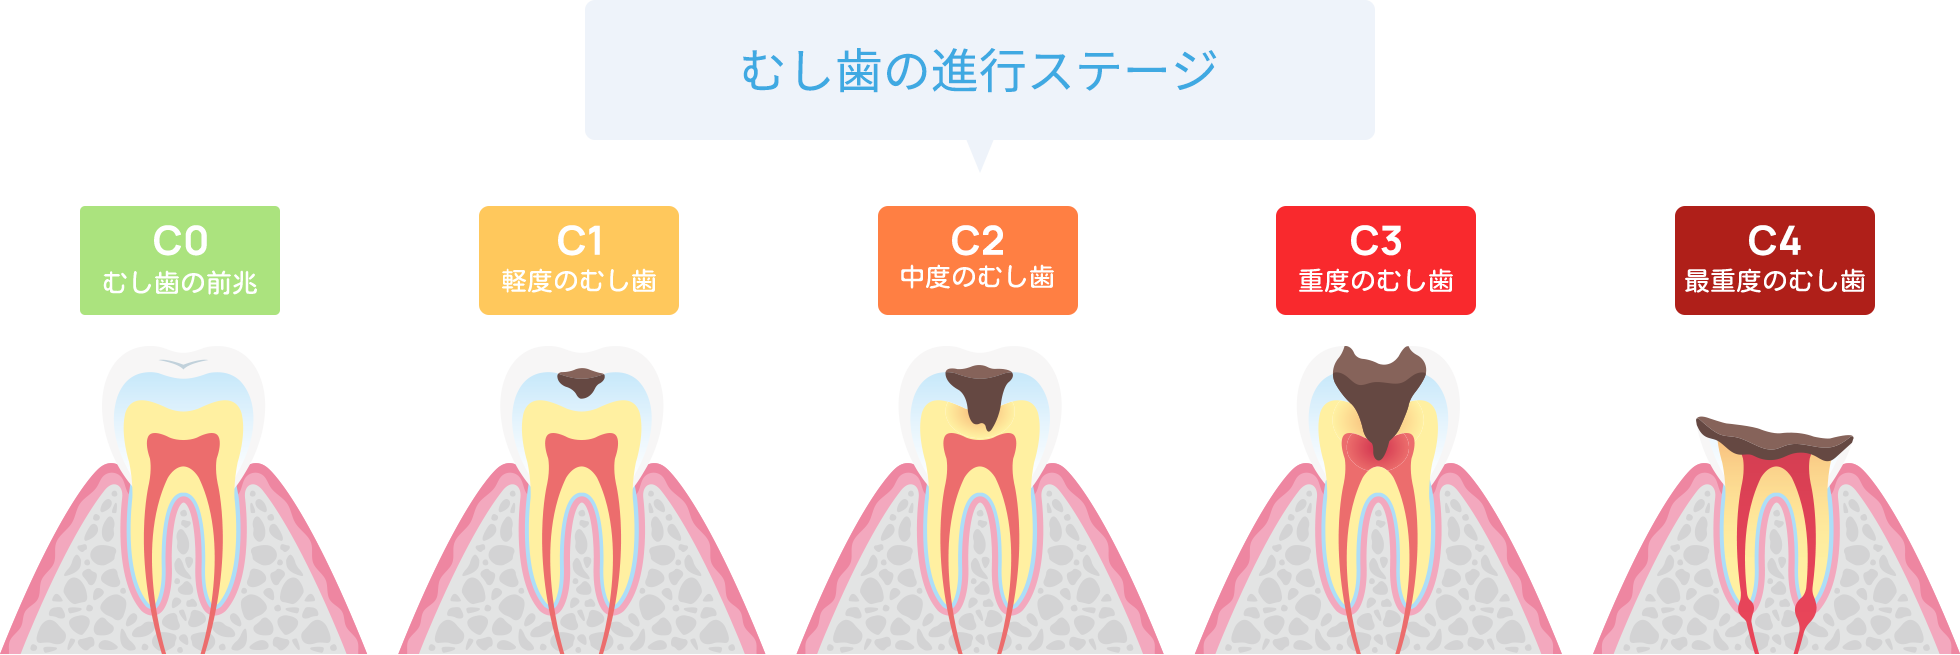

口腔内の糖分を餌に繁殖したミュータンス菌などのむし歯の原因菌が酸を放出し、歯のカルシウムを溶かして穴を空けてしまう病気です。最初は表面のエナメル質を溶かしますが、進行すると象牙質や歯髄にまで進行してしまいます。

進行度によって変わるアプローチ

むし歯は進行度によって治療方法が変わってきます。状態を見極めて治療を選択します。